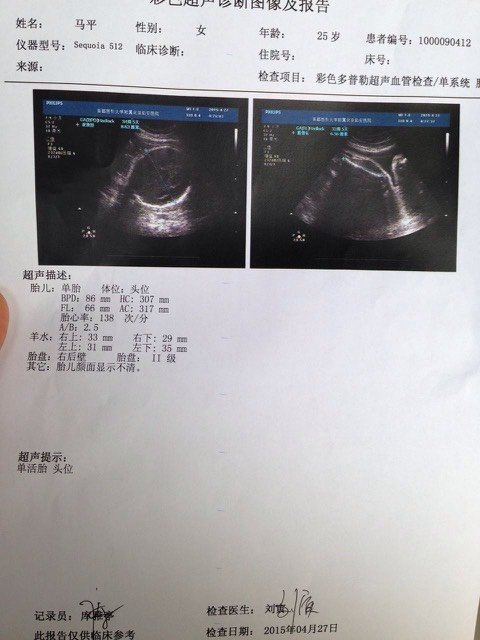

大家给看看男女吧,我很好奇,哈哈 大家给看看男女吧,我很好奇,哈哈 点击展开 畅媳妇 2015-04-27 15:06 为您推荐: 其他回答 是自己的都一样 呵呵 不过我喜欢女儿如我所愿 梧彤雨 2015-04-27 16:18 看不出来的 Amor‘情若相惜、 2015-04-27 15:37 这上面是看不出来的!只要宝宝健康就好 宝贝蛋的妈妈 2015-04-27 15:16 看不出的啦 雪球麻麻 2015-04-27 15:16 看不出来的! 妙妙的麻麻! 2015-04-27 15:10 加载更多 相关问题 我很好奇,想去做个B超,看男女 帮我看看啊~!我很好奇~!高人快来 帮我看看这个问题,非常感谢,我很好奇